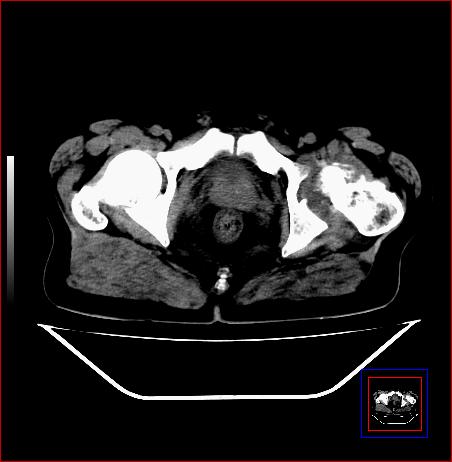

标题: CT15143:髋关节结核?

男,49,髋关节疼痛1年,无肺结核。

支持左侧髋关节结核合并轻度半脱位

骨质破坏,硬化,周围软组织脓肿,支持骨结核

骨质破坏,硬化,周围软组织脓肿,关节间隙增宽,支持骨结核

骨质破坏,硬化,周围软组织脓肿,关节间隙增宽,支持骨结核 .应与无菌坏死鉴别

可以是结核,也可以是无菌坏死,还可以是先天髋关节脱位,不结合临床病史,只凭图像鉴别,请各位老师指教。